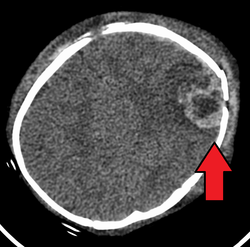

The above CT scan shows an infant having suffered a severe skull fracture and intercranial bleeding from head trauma caused by abusive parenting.